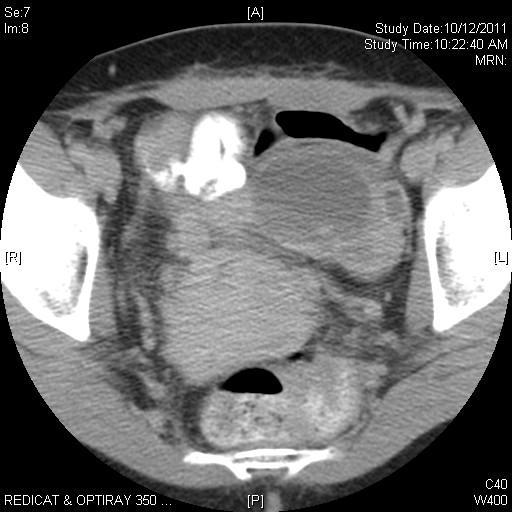

“Suspicious” masses

54yo (CA125=21)

Serous cystadenoma

48yo (CA125=104)

Endometriosis

47yo (CA125=47) Serous adenoca

32yo (CA125=20) Mucinous BT

21yo (CA125=21)

Serous BT